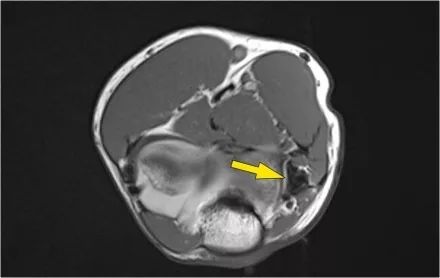

MR-关节造影证实了骨软骨病变。在肱骨和骨软骨病变之间存在钆造影剂,这表明它是不稳定的。注意轴向图像上看到的碎片。